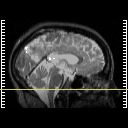

MR Study #3 -- Slice #11

Click on sagittal image to select slice. Click on thin tickmark to change timepoint, or thick tickmark for overlay.